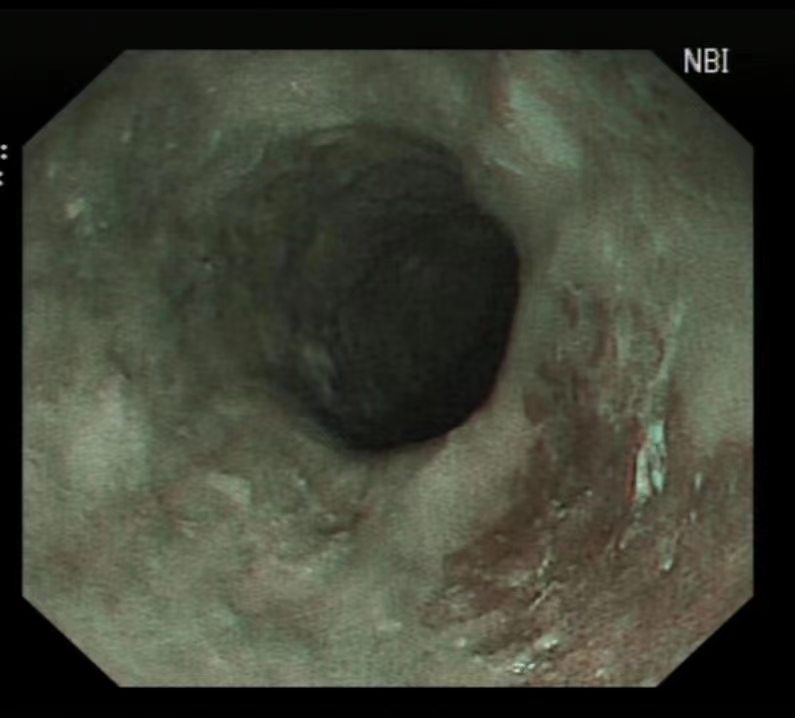

食管早癌 白光

食管早癌NBI